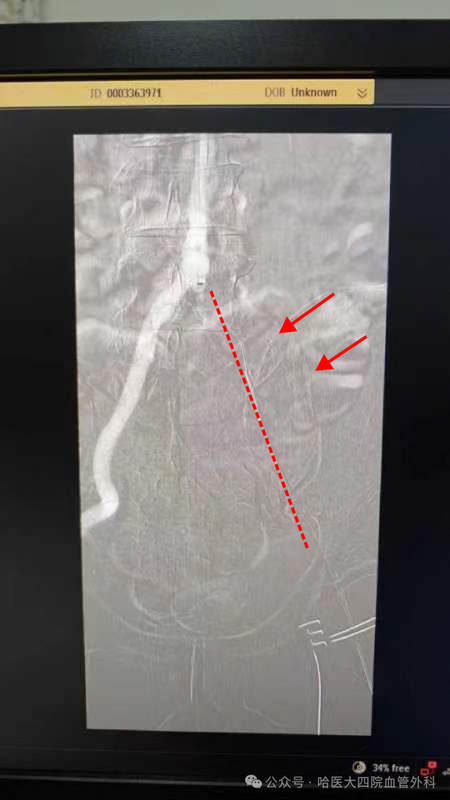

與時(shí)間賽跑——哈醫(yī)大四院血管外科為患者保肢成功

????日前,哈醫(yī)大四院血管外科團(tuán)隊(duì)為一名急性下肢動(dòng)脈血栓患者進(jìn)行手術(shù)治療,成功的開通患者下肢血管,避免患者截肢。??王大爺今年70歲,一天前左下肢突然疼痛,麻木,發(fā)涼,于當(dāng)?shù)蒯t(yī)院就診,行彩超檢查提示下肢動(dòng)脈栓塞,醫(yī)生建議患者盡快轉(zhuǎn)院治療。當(dāng)?shù)蒯t(yī)院將張大娘轉(zhuǎn)診至哈醫(yī)大四院血管外科。黃任平主任為患者仔細(xì)檢查并做術(shù)前評估,考慮患者既往房顫病史,左髂動(dòng)脈栓塞可能與房顫形成血栓脫落導(dǎo)致,應(yīng)盡早手術(shù)治療,如延誤手術(shù)時(shí)機(jī)可導(dǎo)致下肢缺血時(shí)間過長,有截肢風(fēng)險(xiǎn)。經(jīng)過縝密的術(shù)前準(zhǔn)備,血管外科團(tuán)隊(duì)為患者行左下肢動(dòng)脈切開取栓,動(dòng)脈造影,球囊擴(kuò)張支架置入術(shù),術(shù)中取出大量新鮮血栓,術(shù)后患者下肢涼麻及疼痛的感覺立刻消失,左側(cè)下肢動(dòng)脈也恢復(fù)了搏動(dòng)。目前患者恢復(fù)良好,即將出院。黃任平主任介紹,房顫是導(dǎo)致下肢動(dòng)脈栓塞的元兇,多數(shù)患者急性發(fā)病。下肢動(dòng)脈栓塞會導(dǎo)致下肢缺血,導(dǎo)致下肢疼痛,涼,麻,皮膚蒼白,觸及不到脈搏等癥狀,經(jīng)常有患者因沒有及時(shí)就醫(yī)而錯(cuò)失最佳治療時(shí)機(jī),最終截肢。解決栓塞的主要方法是盡早開通血管,恢復(fù)血液供應(yīng)。傳統(tǒng)的方法是開刀手術(shù)取栓,因多數(shù)患者伴有心臟疾病,圍手術(shù)期風(fēng)險(xiǎn)極高。哈醫(yī)大血管外科開展了目前國際上最先進(jìn)的微創(chuàng)血栓抽吸方法,不開刀,經(jīng)過一根細(xì)管就可以把血栓抽吸出來,避免了開刀手術(shù)及麻醉時(shí)間過長對患者造成的打擊,留因此當(dāng)患者突然發(fā)生下肢疼痛,涼伴麻木等癥狀時(shí),不要忽視下肢動(dòng)脈栓塞的可能,應(yīng)盡早就醫(yī),避免病情加重,失去肢體。